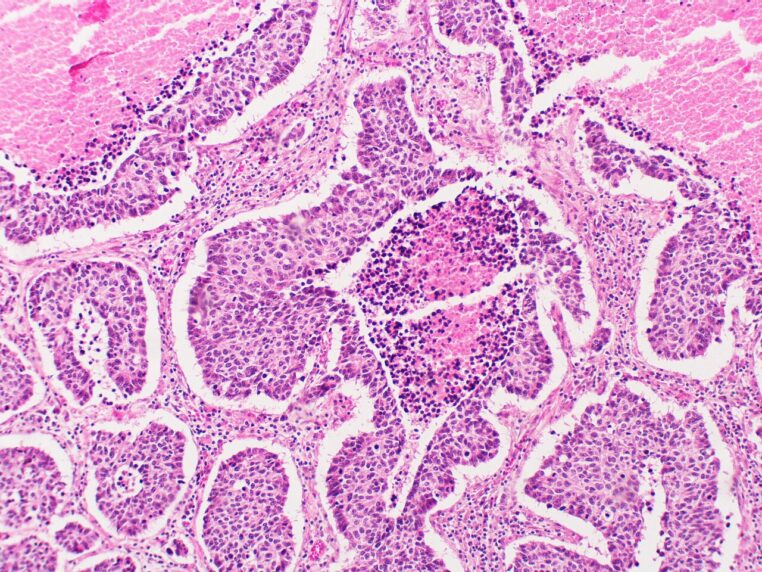

Longtemps classés parmi les cancers rares. Les cancers neuroendocriniens (ou néoplasmes neuroendocriniens) sont en réalité un ensemble de tumeurs très hétérogènes. Ils naissent à partir de cellules dites « neuroendocrines », à cheval entre système nerveux et système hormonal. Capables de produire des messagers chimiques. On les retrouve surtout dans le tube digestif, le pancréas et les poumons. Mais ils peuvent apparaître presque partout dans l’organisme.

On parle souvent, pour simplifier, de deux grandes catégories. D’un côté, les tumeurs neuroendocrines (TNE/NET), souvent plus lentes, parfois « silencieuses » pendant longtemps. De l’autre, les carcinomes neuroendocriniens (CNE/NEC), plus agressifs et à croissance rapide, qui exigent une prise en charge urgente.

Or, même cette distinction ne suffit pas à décrire la complexité des cas. Le site d’information de NCUK et les documents de réseaux spécialisés comme UKINETS rappellent que ces cancers regroupent des formes multiples. Comme on peut en trouver pour le cancer colorectal, des localisations variées. Et des trajectoires très différentes, ce qui complique la vigilance en médecine générale.